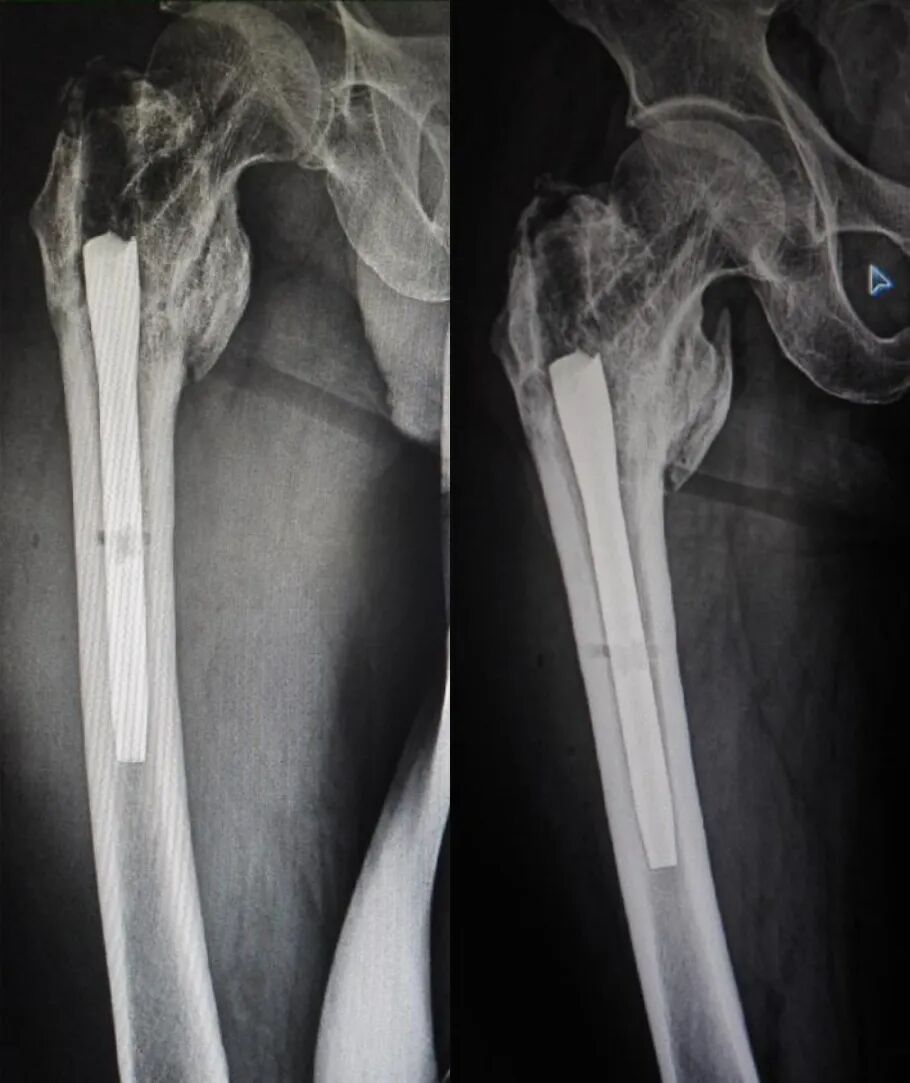

术后 21 个月 X 线片:

患者术后一年半有余,要求去除内固定物来院,未诉不适,大意了,术前阅片不仔细,术中拆除锁钉、螺旋刀片和尾帽,拔主钉后傻眼了 —— 只拔出了上三分之一 ,回头再看片子才发现主钉刚好在螺旋刀片处断裂了。

之前就看骨折愈合得很好,时间也够,当小菜一碟,没有仔细阅片,术中很是被动,想过取,感觉创伤太大,仔细与患者沟通,建议患者不取了,家属也签字了,结果术后还是纠缠不休,最后免费治疗,赔钱走人。教训是惨痛的啊!